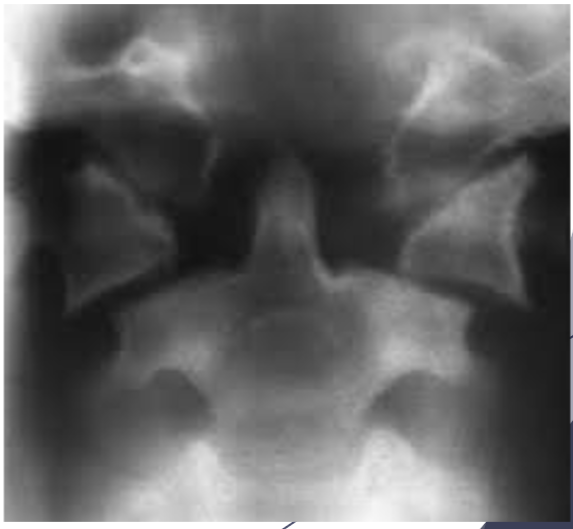

Masculino, 12 anos

Síndrome da sincondrose isquiopúbica assimétrica (Doença de Van Neck-Odelberg)

Variante da normalidade (em geral assintomático)

Crianças

Alargamento e radioluscência na sincondrose isquiopúbica, que simula neoplasias, infecção;